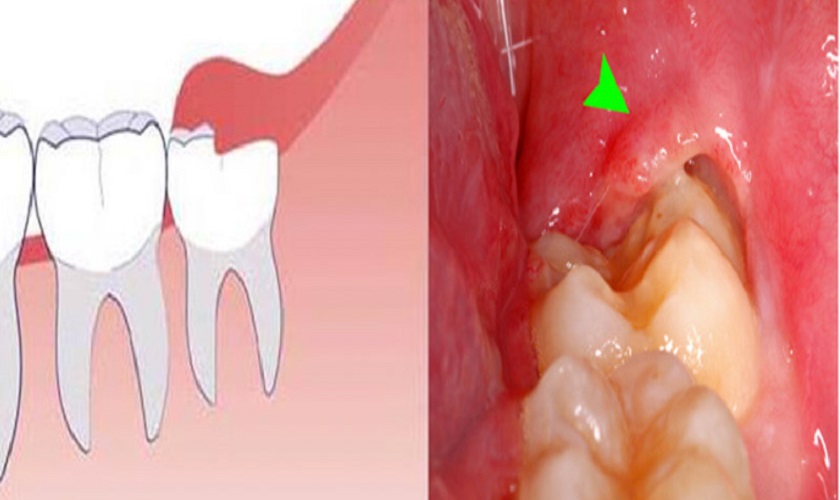

Viêm nướu, viêm lợi trùm có dấu hiệu áp xe, chảy mủ, sưng tấy vùng nướu

Viêm nướu và viêm lợi trùm là những tình trạng phát sinh thường gặp khi răng khôn mọc lên. Trong trường hợp răng khôn chưa mọc hoàn chỉnh, lợi có thể bị viêm, sưng và tạo ra áp xe, khiến cho người bệnh cảm thấy đau đớn. Tình trạng này không chỉ gây khó chịu mà còn có thể gây ra những biến chứng khó lường khác.

Người bệnh có thể thấy triệu chứng chảy mủ, sưng tấy vùng nướu gần răng khôn. Nếu không được xử lý kịp thời, tình trạng này có thể dẫn đến nhiễm trùng lan rộng đến các vùng khác trong miệng và thậm chí có thể cần phải điều trị kháng sinh mạnh. Những vấn đề về viêm nhiễm không chỉ ảnh hưởng đến sức khỏe răng miệng mà còn tiềm ẩn nguy cơ ảnh hưởng đến sức khỏe toàn thân nếu để lâu dài.